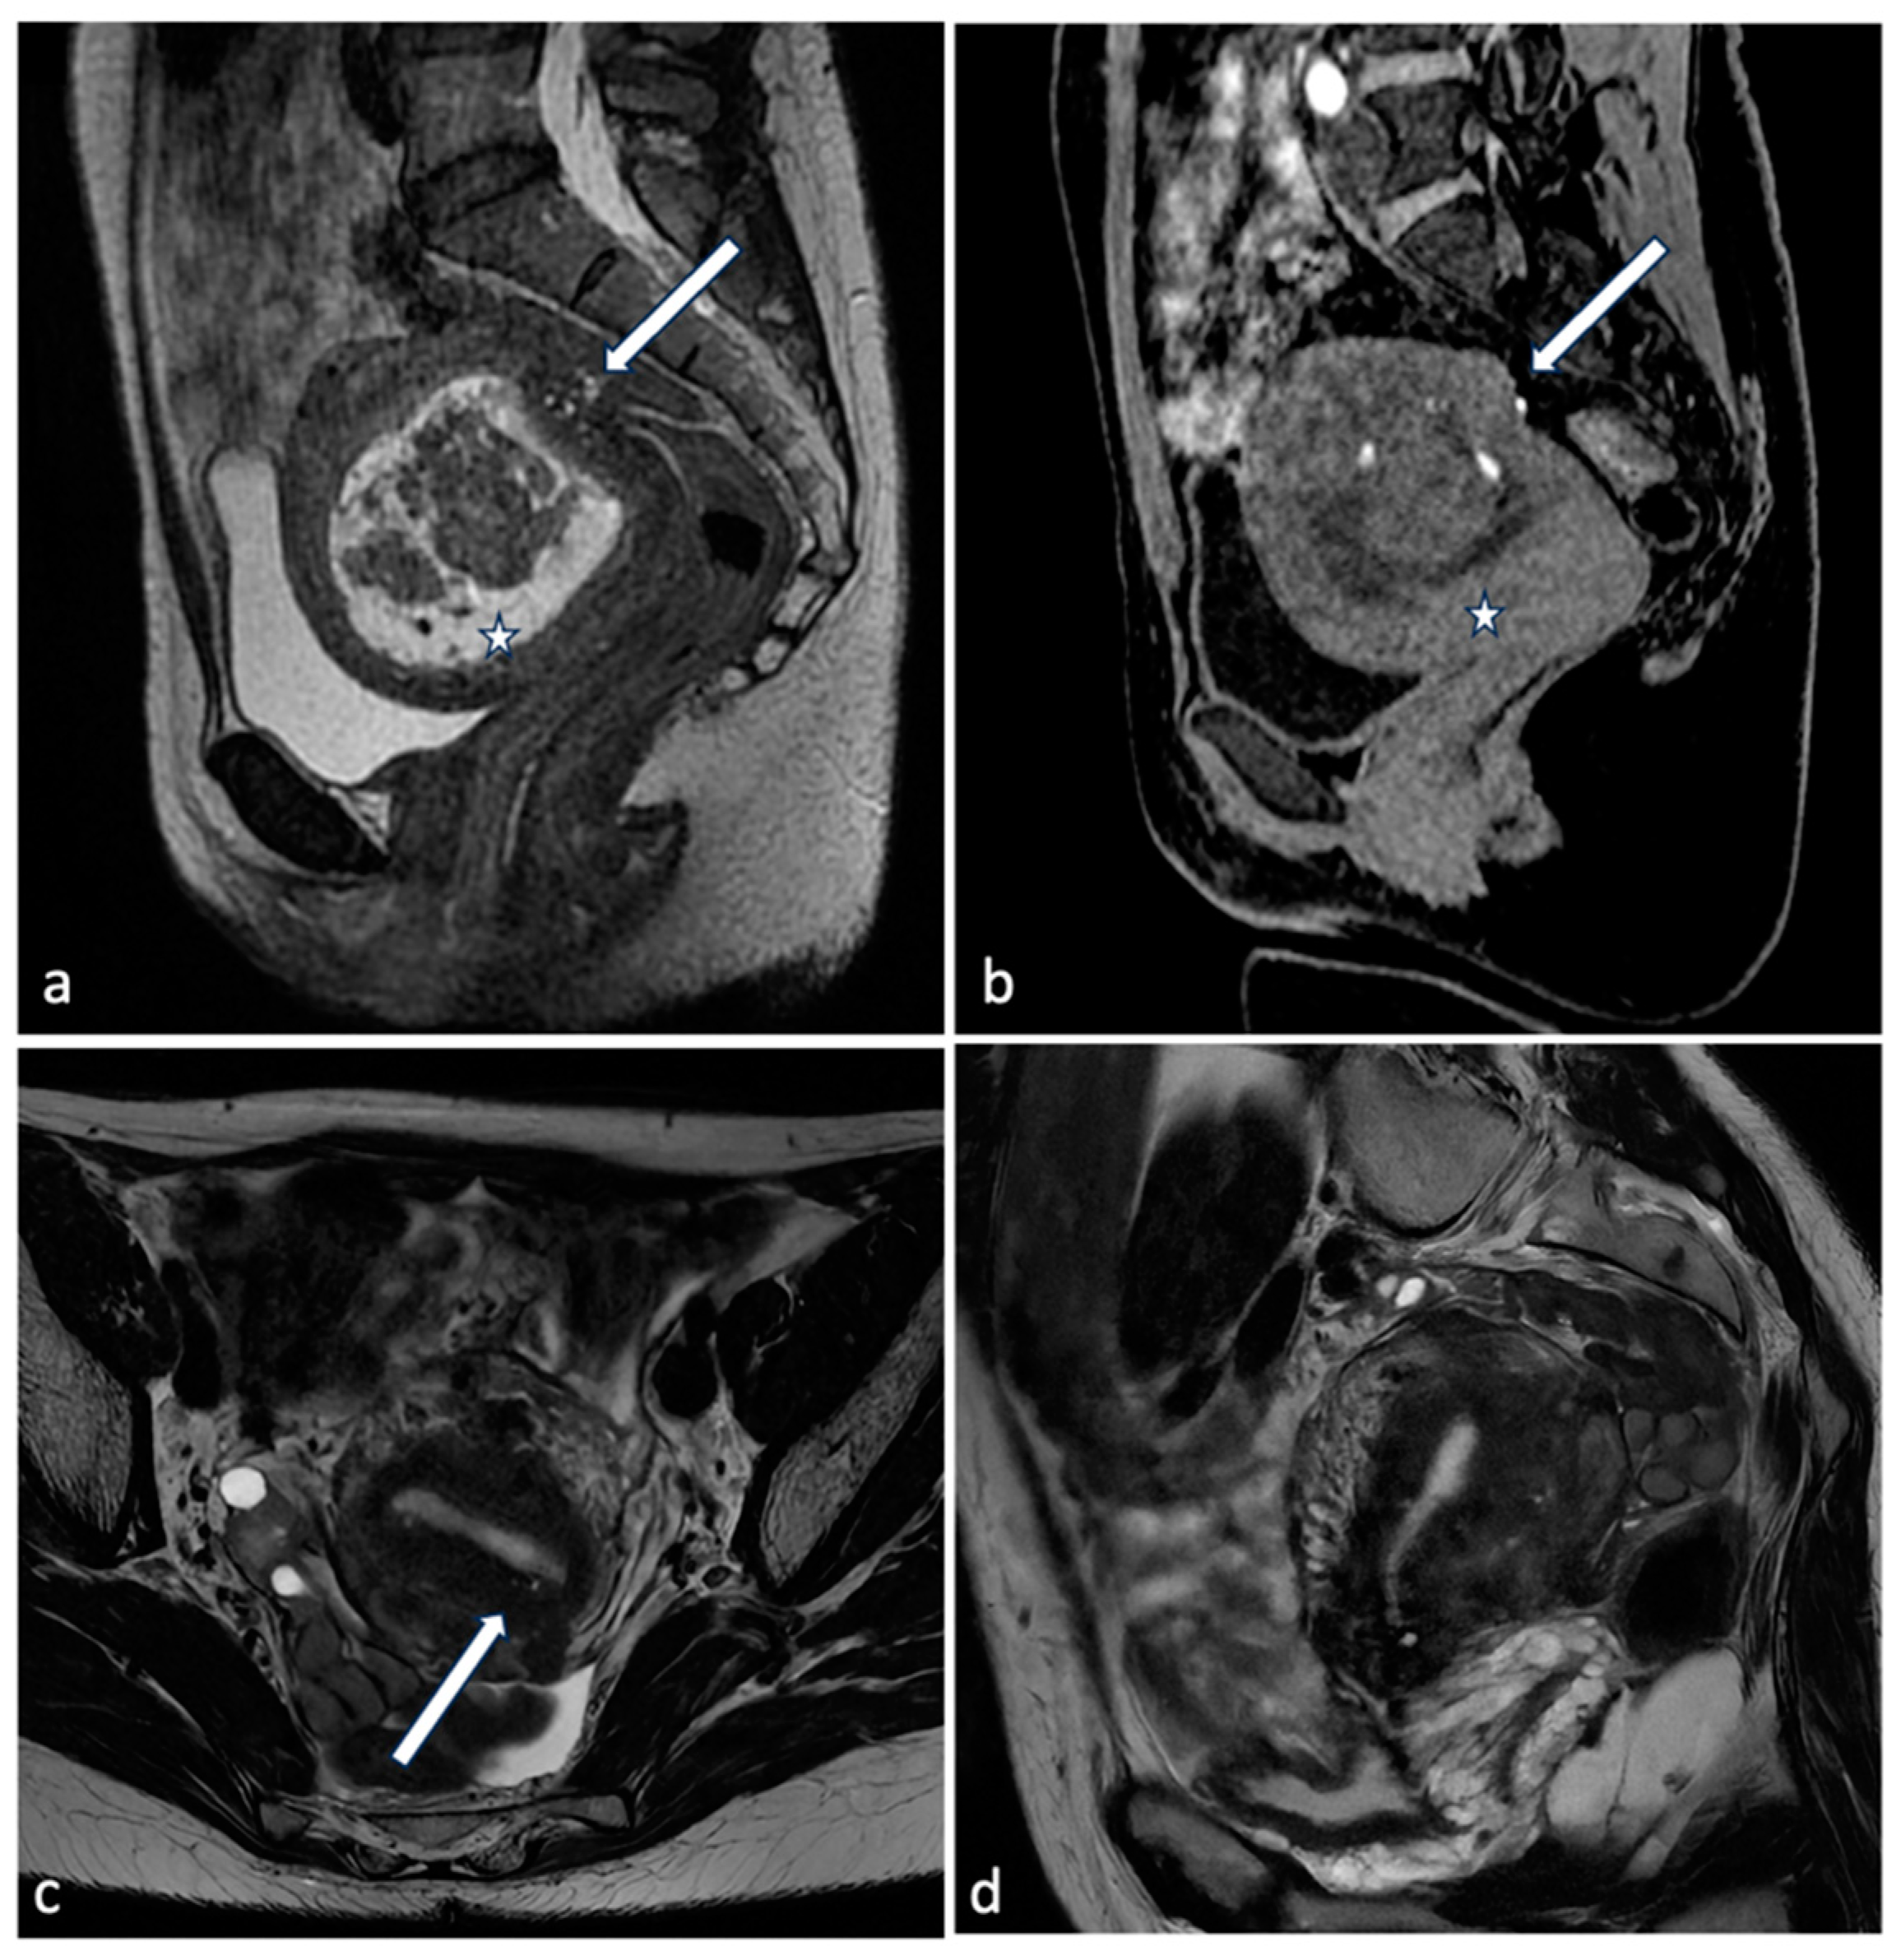

Figure 2.

Different endometriosis phenotypes. A 41-year-old patient with a history of infertility, menometrorrhagias and chronic pelvic pain: MRI shows on sagittal CUBE T2WI (a, arrow) an extensive posterior external adenomyosis with bright foci on T1WI (b, arrow). There was associated deep pelvic infiltrating endometriosis and a large submucosal leiomyoma (a,b, star). Another 50-year-old patient with history of metrorrhagias: MRI demonstrates on axial T2WI (c) internal diffuse adenomyosis with hyperintense foci within the JZ (arrow). Sagittal T2 sequence (d) shows a diffuse thickening of the JZ (15 mm), prevalent on the posterior wall.